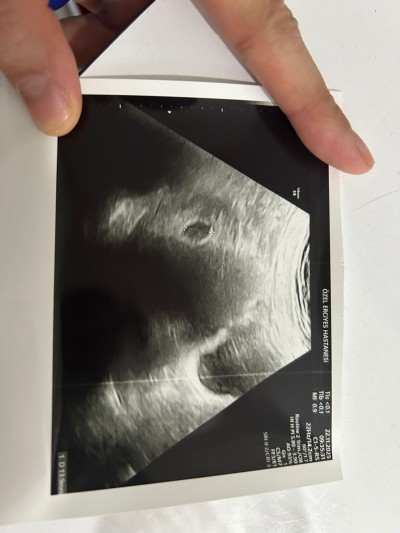

MERHABA,

6+3 DE GİTTİĞİMDE GÖRÜNTÜ BU ŞEKİLDE. KALP ATIŞI VE BEBİŞ GÖZÜKMEDİ HENÜZ. GELECEK HAFTA TEKRAR GİDECEĞİM. 1.SORUM NORMAL Mİ? 2.SORUM DA ZOOM YAPIP BAKINCA UZUNLUK ÖLÇÜSÜNÜN SAĞ TARAFINDA YOLK SAC MI VAR YOKSA SÜREKLİ BAKMAKTAN BEYNİM BANA OYUN MU OYNUYOR??

Gebelik haftası 6

Merhaba dun bende gittim 6+3 doktor bakti kese gozukuyor 14 mml dedi ama bebek yok 10 gun sonra gel dedi yine bakariz bende 9 gun sonraya randevu aldim ilk cocuktadada bende hatirladigim kadariyla yine keseydi bebek gozukmemisti ama dun cox stres oldum

Benimki de tam öyle 14 mm çıktı baktıkça bir şeyler görüyorum